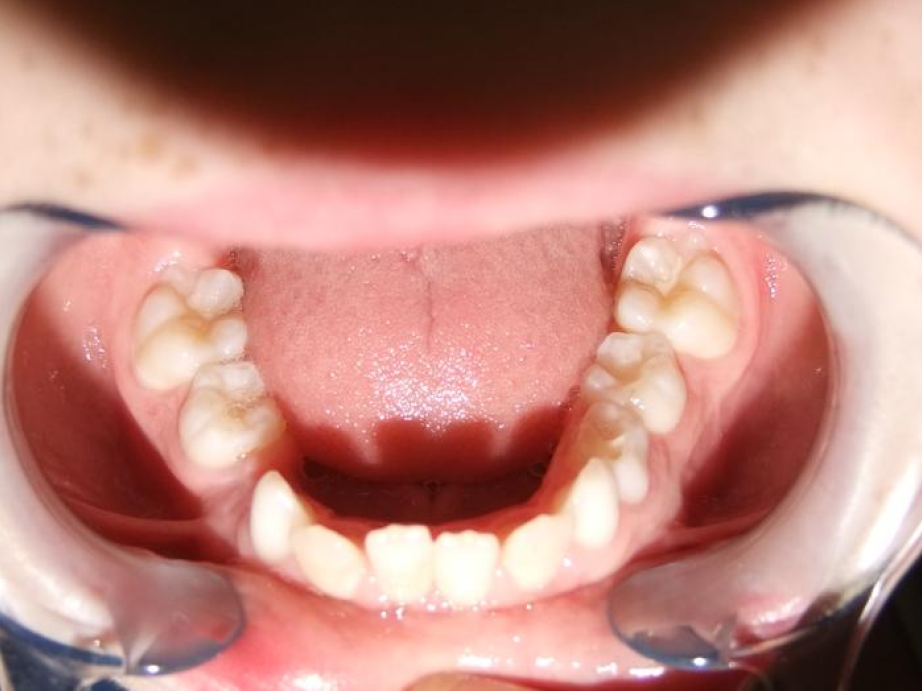

eindfoto

Leeftijd bij aanvang: 9 jaar

1-6 Bonded Hyrax + partieel vast onderkaak + TransForce onderkaak

7-13 Twinblock

13-22 volledig vast onder- en bovenkaak + rotator

Retentie: wrap en c-c bar

Leeftijd bij retentie: 12 jaar